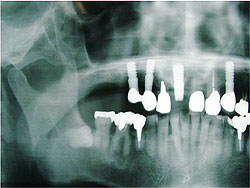

AQBは、結晶体の密度が高く純度も高いことが特長であり、三井記念病院におけるAQBインプラント症例では、最長18年を経過した臨床例においても、歯槽骨の状態は変わらず、逆に密になっていることが分かっている。そこで、上顎臼歯部の骨吸収症例において、サイナスリフトと同時にAQBインプラント1ピースを植立し、自家骨移植や人工骨移植を行わず、治療を行った症例を報告した。6例に施行し、全例、予後良好で、すべて植立後4ヵ月以内で咬合を開始した。GBR症例においてもAQBインプラント2ピースを埋入し、自家骨移植や人工骨移植は行わず、チタン入り非吸収性膜を用いたスペースメーキングを行った。その結果、4ヵ月後には歯槽骨の再生を確認した。

| AQBを用いて歯槽骨再生を図った症例 | |

サイナスリフト症例 ▼ ![]() 術前 ![]() 術直後 ![]() 術後4ヵ月 |